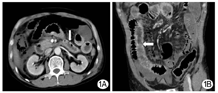

患者男性,47岁,因"持续性腹胀、腹痛3 d,症状加重伴黑便1 d"急诊入院,既往有痛风10余年,长期服用强的松、保泰松、布洛芬治疗,余无特殊病史。入院查体:体温38.5℃,脉搏110次/min,呼吸26次/min,血压90/65 mmHg(1 mmHg=0.133 kPa),意识清楚,稍烦躁,皮肤巩膜无黄染,双肺呼吸音粗,全腹稍膨隆,上腹部压痛明显,轻度肌紧张,肠鸣音1~2次/min。实验室检查:白细胞2.85×109/L,血小板30×109/L,谷丙转氨酶115 U/L,谷草转氨酶419 U/L,血尿素氮16.8 mmol/L,肌酐439 μmol/L,Ca2+ 1.65 mmol/L,淀粉酶2 790 U/L,血糖12.8 mmol/L,降钙素原80.91 μg/L,脑钠肽9 719 pg/ml。入院诊断为急性胰腺炎、休克代偿期、MODS、痛风。积极采取禁食、胃肠减压、解痉镇痛、抑制胰液分泌、补液扩容、营养支持和中药等综合治疗措施,病情无缓解,腹痛、腹胀进一步加重。入院后10 h腹部增强CT报告:小肠不全性梗阻,左中上腹小肠肠壁下积气,肠坏死可能;右中下腹小肠肠壁异常强化,考虑炎性病变;腹腔积液;胰体、尾部强化不均匀伴周围积液,双侧胸腔积液(图1)。诊断性腹腔穿刺抽出暗红色血性液体,考虑SAP合并肠坏死可能。征得家属同意,急诊剖腹探查,术中发现约有100 cm的末端回肠坏死和右半结肠坏死,胰体、尾部坏死。行末端回肠切除术+右半结肠切除术+胰体尾坏死组织清除胰周引流术+回肠造瘘术。术后转ICU进一步治疗,因病情重,术后第3天因多器官功能衰竭死亡。术后病理示肠壁细胞坏死,大量炎性细胞浸润(图2)。

1A:冠状位影像提示小肠不全性梗阻,左、中上腹小肠肠壁下积气,肠坏死可能(箭头所示);1B:矢状位影像提示右中下腹小肠肠壁异常强化,考虑炎性病变(箭头所示),腹腔积液